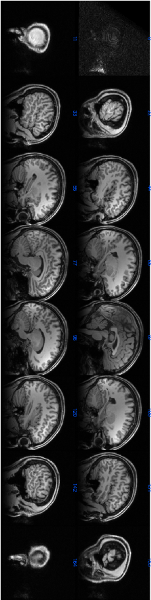

- Brain MR image processing and application of classification algorithms for the detection of brain neuronal disorders. Testing of new multishell brain HARDI models.

- MR image processing and application of classification algorithms for the detection of brain neuronal disorders.

- Automatic segmentation of brain tumors using tensor analysis and multimodal MRI

- Neurocognitive disorder detection based on Feature Vectors extracted from VBM analysis of structural MRI

- Neural classifiers for schizophrenia diagnostic support on diffusion imaging data

- Machine Learning Approach for Myotonic Dystrophy Diagnostic Support from MRI